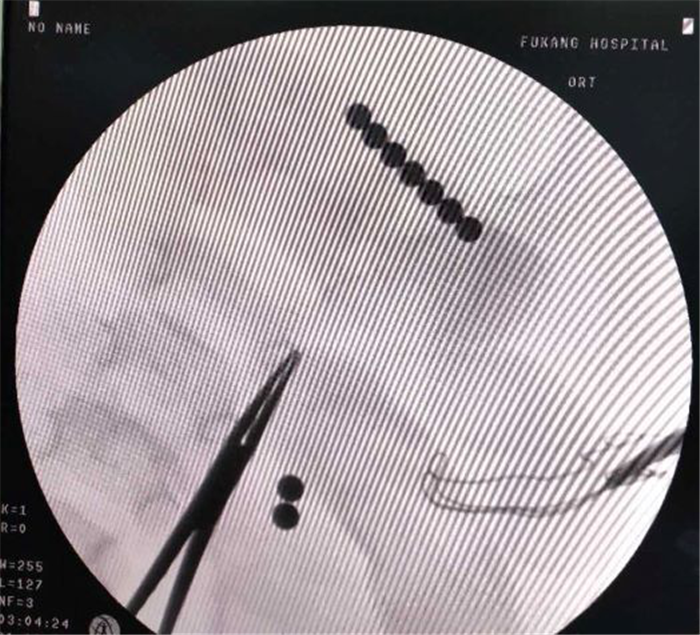

(圖4)腸道內(nèi)的“磁力珠”

普外科陳主任主刀,閆孟主治醫(yī)師一助,王進坤主治醫(yī)師二助,術(shù)中發(fā)現(xiàn)因直徑5mm彩色“磁力珠”長時間在腸道內(nèi),已造成腸內(nèi)5處穿孔,其中2粒在空腸,7粒在升結(jié)腸(圖4),空腸3處穿孔,升結(jié)腸2處穿孔,腸系膜廣泛淋巴結(jié)腫大,幸運的是穿孔直徑均在2mm以下,患兒納差,大便干結(jié),無食物殘渣、糞便及較多腸液進入腹腔,腹腔僅約100ml淡黃色清亮滲液,沒有明顯的腹腔污染,為其行“腸腔異物取出術(shù)+腸穿孔修補術(shù)+腹腔沖洗引流術(shù)”,成功取出腸腔內(nèi)9枚彩色圓形金屬異物(圖1)。